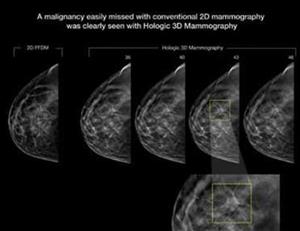

3D Mammography/Breast Tomosynthesis

With a continued and dedicated interest in supporting and caring for the women in our community, Sansum Clinic has – with the help of gifts from grateful patient – invested in new 3D Mammography technology, or Breast Tomosynthesis. Our standard 2D digital mammographic imaging has been, and is, an amazing tool for the early detection of cancers. Upgrading to this new 3D technology, the Selenia Dimensions from Hologic®, can help us detect cancers much earlier and those cancers can be caught when they are much smaller, making them easier to treat. A recent article, “Breast Cancer Screening Using Tomosynthesis in Combination with Digital Mammography” from the Journal of the American Medical Association (JAMA, June 25, 2014) highlights the distinct benefit of the technology after a total of 454,850 examinations (281,187 conventional mammograms compared to 173,663 3D mammograms) were conducted. A few of the significant findings are:

- A 41% increase in the detection of invasive breast cancers

- A 29% increase in the detection of all breast cancers

- A 15% decrease in women recalled for additional imaging

An increase in the number of cancers detected is significant and the benefit may seem obvious to those reading this article. Maybe not so obvious in significance is the decrease in the number of women recalled for additional imaging. This means that we can effectively reduce the radiation exposure from additional imaging, and perhaps more importantly, reduce the worry, anxiety and stress among our patients associated with those callbacks.